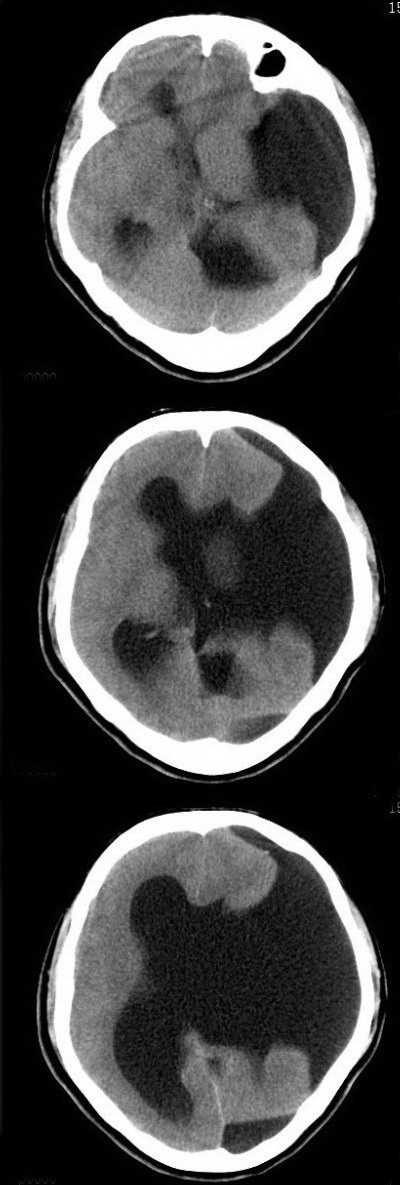

标题: CT16833:F34Y,左侧积水型无脑畸形?请指教. [打印本页]

标题: CT16833:F34Y,左侧积水型无脑畸形?请指教.

女.34.自幼右下肢跛行.智力正常,未发现其它不适。

左侧脑裂畸形(完全型、分离型)。

脑裂畸形是一种大脑发育畸形,发生于妊娠的前两个月,系因局部脑组织生长、分化受阻所致。与无脑回畸形、多微脑回畸形、巨脑回畸形、灰质异位症同属神经元移行异常。

胎儿期第8周,成神经细胞开始从中线移行至外周以形成脑皮层,如任何原因所致移行障碍或停止,则神经元停留在皮层下不同水平,如移行停止仅位于局部,则脑皮层灶性缺乏,可形成残余软脑膜室管膜缝,这种异常称为脑裂畸形,可分为分离型及融合型两型。但其病因目前尚不甚清楚,可能与缺血、感染或某些理化因素有关。同一病因,作用于迁移运动的不同阶段,或病因轻重不同,可导致不同类型的神经元移行异常。

脑裂畸形基本改变为横贯大脑半球的裂隙,其外端的软脑膜与内端的室管膜通过裂隙相连接,形成软脑膜—室管膜缝(p-e缝)。分离型裂隙在ct上可清晰显现,不难诊断。融合型裂隙,在ct上则易漏诊。但如发现横贯大脑半球的与灰质密度相同的带状影,其外端脑表面出现凹陷,内端脑室呈现天幕状憩室,即可作出正确诊断。

脑裂畸形常合并多微脑回畸形、透明隔和胼胝体畸形。

脑裂畸形鉴别诊断不难,主要与脑穿通畸形等大脑发育成熟后的损害相鉴别。裂隙壁的异位灰质的密度无论是平扫还是增强扫描都与脑皮层相同或相似,是鉴别的关键。